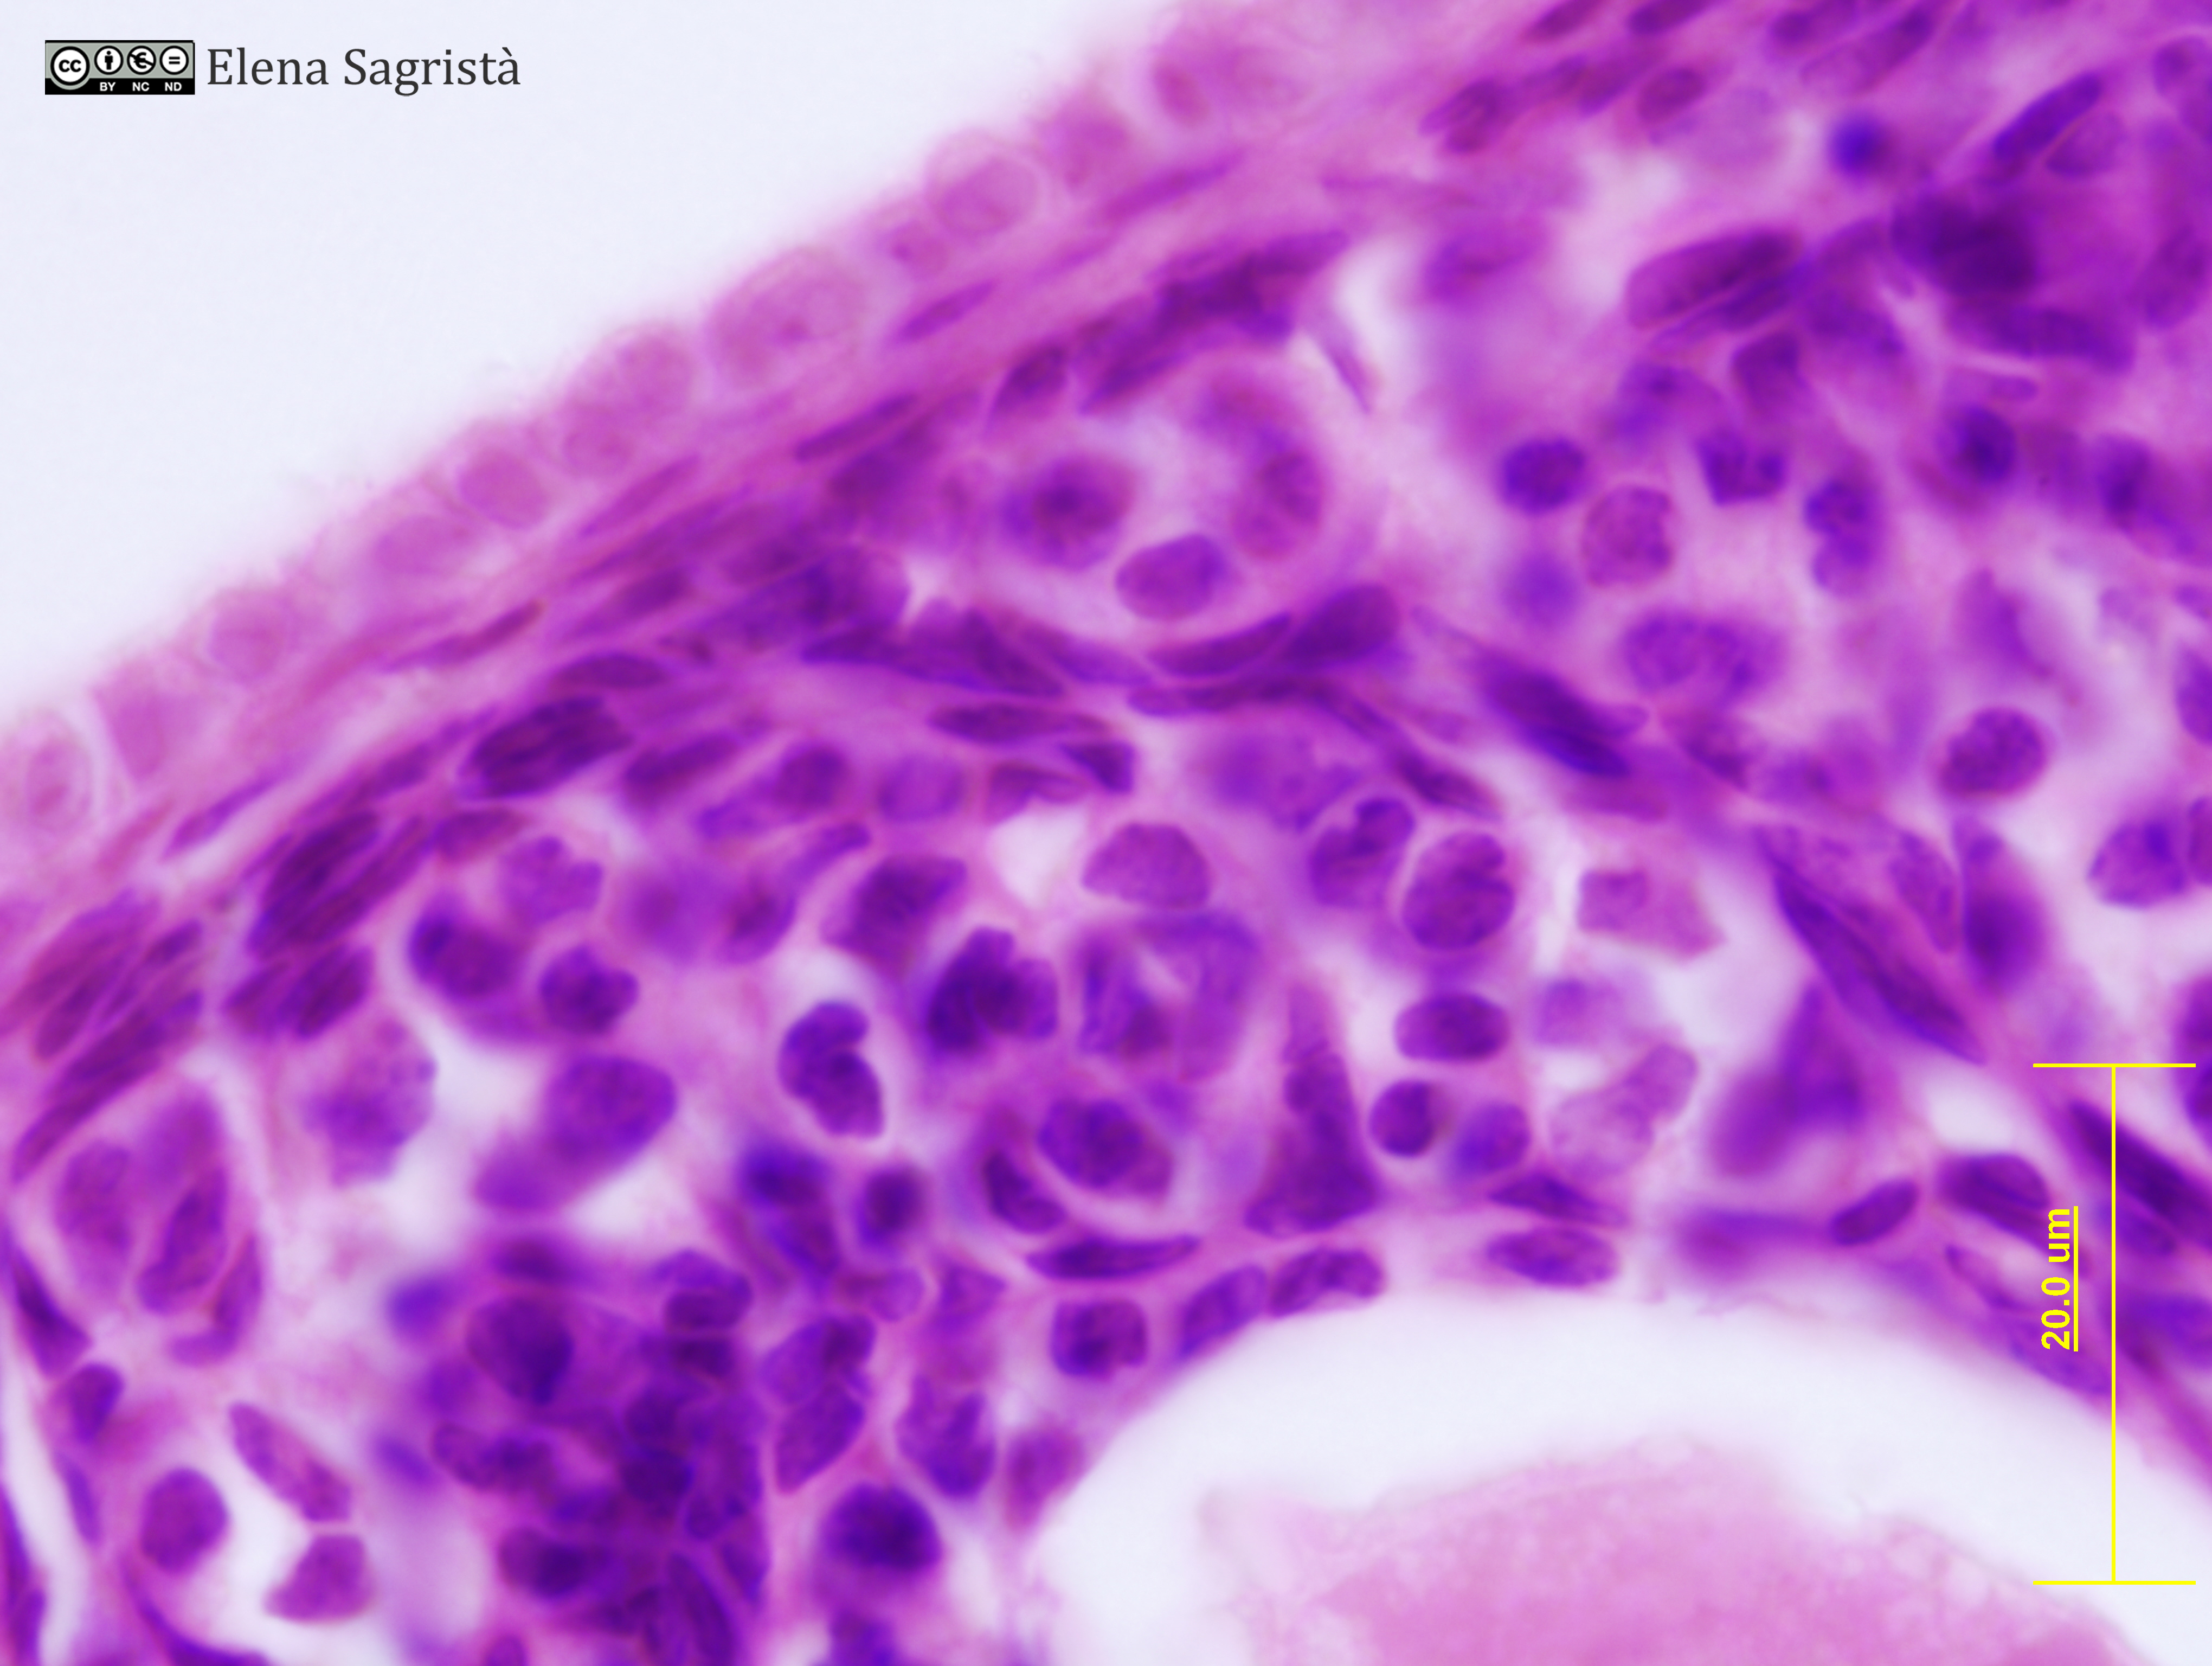

Imatges de preparacions histològiques d'Ovari i Aparell reproductor femení. Microscòpia òptica.